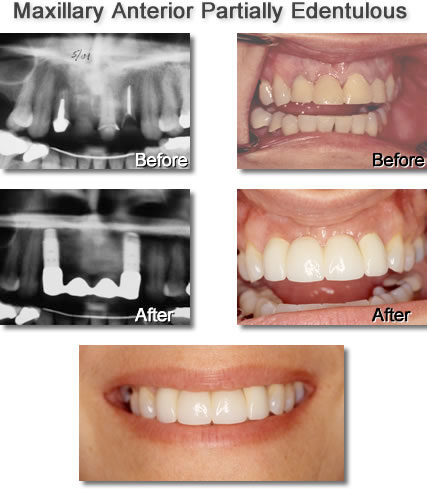

Multiple-tooth Implants

Replacing Multiple Missing Teeth in One Area of the Mouth

Historically multiple missing teeth have been replaced with a removable prosthesis (often called a partial denture) or with a Fixed Bridge. A Fixed Bridge requires the dentist to alter good teeth adjacent to the area of missing teeth.

The ideal way to replace multiple missing teeth is to place dental implants. This avoids the altering of the patient's natural teeth and provides a restoration that has greater longevity. The number of implants required will be determined by the number of teeth to be replaced as well as the quality of the bone.